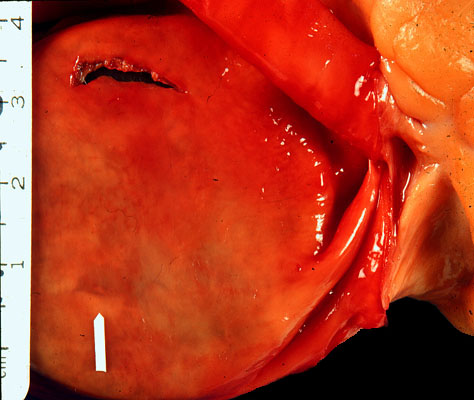

Intimal tear of the aorta in Marfan syndrome

The intima shows a tear where the patient bled to death through this ruptured aorta.